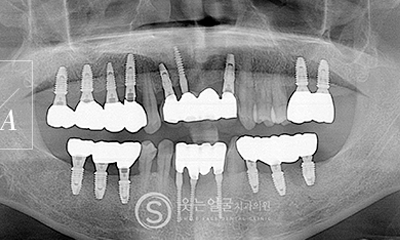

한눈에 보는

임플란트 전후사진